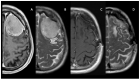

(1) Background: More than one-third of patients with meningiomas experience at least one seizure during the course of their disease, and in the 20-50% of cases, seizure represents the onset symptom. After surgery, up to 30% of patients continue to have seizures, while others may experience them later; (2) Methods: The study analyzed retrospectively the risk factors for pre-operative seizures in a large cohort of 358 patients who underwent surgery for newly diagnosed brain meningioma; (3) Results: We identified age, peritumor edema, and location as risk factors for seizure at the onset. Patients with seizures differed from patients without seizures for the following characteristics: younger average age, lower pre-operative Karnofsky Performance Status (KPS), location on the convexity, lower Simpson Grade, lower incidence of pre-operative neurological deficits, and higher incidence of pre-operative peritumor edema. After 24 months, 88.2% of patients were classified as Engel class Ia, and no correlation with disease progression was observed; (4) Conclusions: Meningioma-related epilepsy has generally a positive outcome following surgery and it seems not to be linked to disease progression, even if further studies are needed.